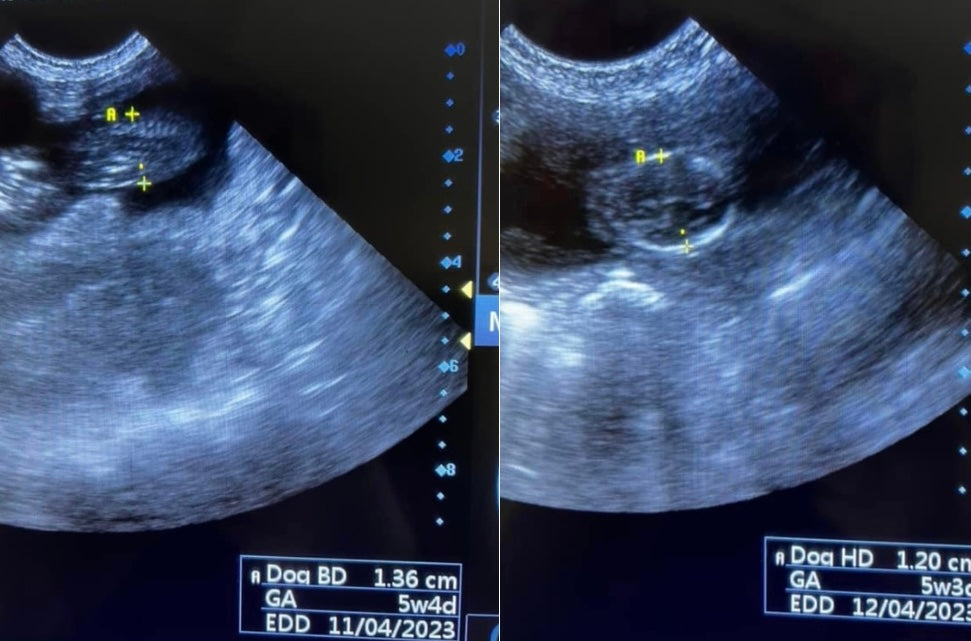

We can measure the puppies gestation a few ways in ultrasound Scanning.

The four main Indicators used for Gestational Age are: